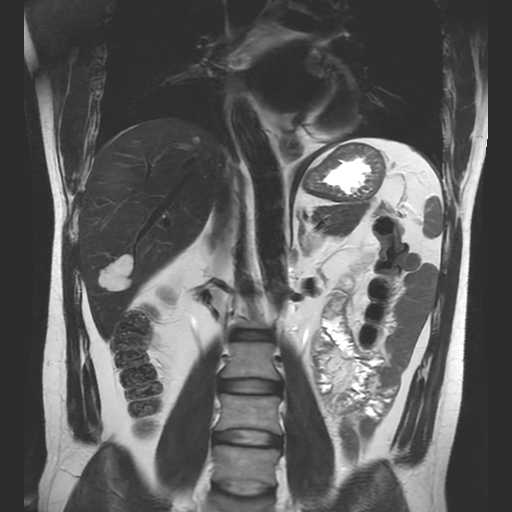

MRI検査

内科領域

腹部

肝血管腫

膵管内乳頭粘液性腫瘍(IPMN)